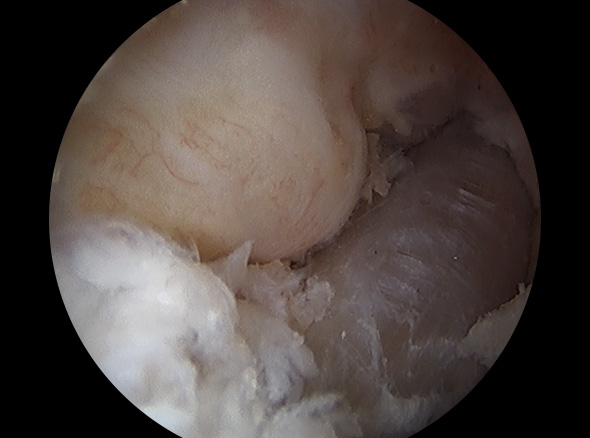

경골과 대퇴골 사이에 남아 있는 전방십자인대 제거

경골과 대퇴골 사이에